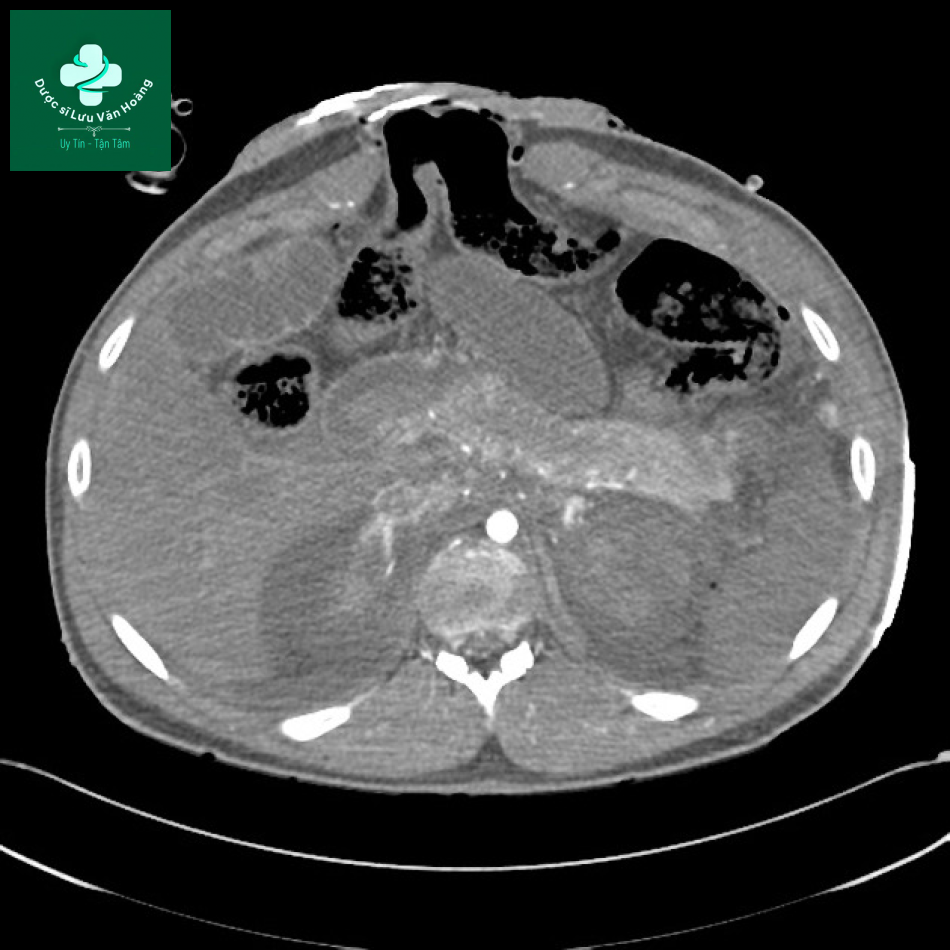

Một trường hợp sốc ruột. Tĩnh mạch chủ dưới xẹp gần như hoàn toàn.

Ví dụ 4

Bệnh nhân nam, 25 tuổi. Lớp niêm mạc hồi tràng dày lên và ngấm thuốc. Tĩnh mạch chủ dưới xẹp và giảm đường kính động mạch chủ.